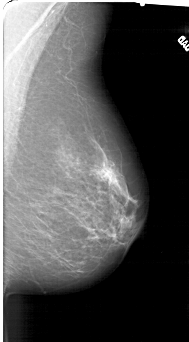

A_1415_1.RIGHT_MLO

RIGHT_MLO LINES 6151 PIXELS_PER_LINE 3391 BITS_PER_PIXEL 12 RESOLUTION 43.5 NON_OVERLAY